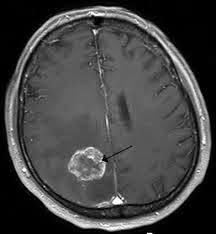

4. Uvimbe ndani ya ubongo i.e brain tumour